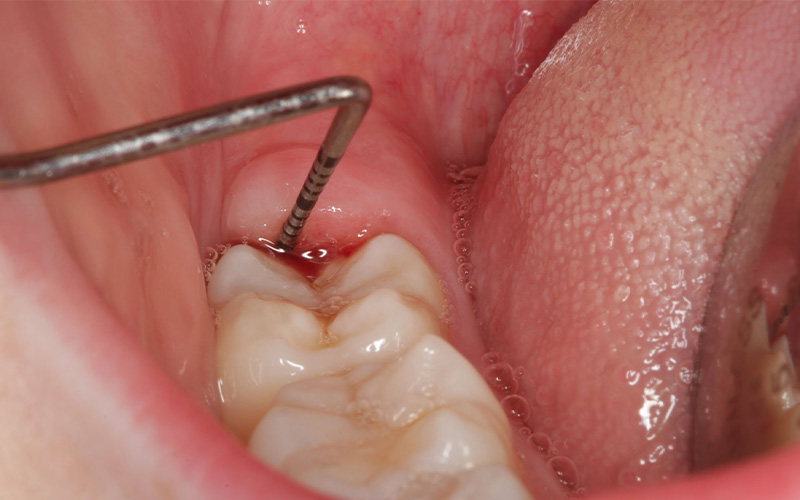

4. پریکرونیت چگونه تشخیص داده می شود؟

عفونت دندان عقل با معاینه دندانپزشکی و در برخی موارد تصویربرداری با اشعه ایکس برای بررسی موقعیت دندان عقل تشخیص داده می شود.